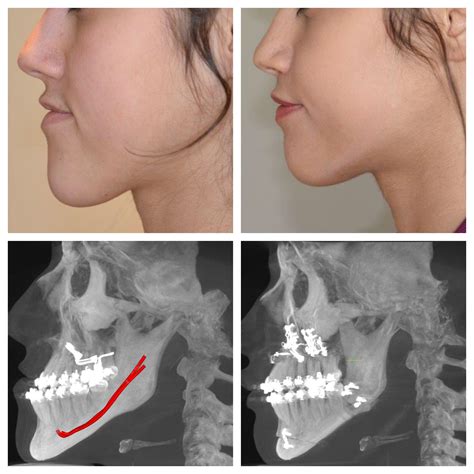

Orthognathic surgery, often referred to as corrective jaw surgery, is a procedure designed to correct a wide range of skeletal and dental irregularities. These issues can include misaligned jaws, malocclusions, and facial asymmetries. While the benefits of orthognathic surgery are numerous, one of the most significant considerations for patients is the Orthognathic Surgery Cost. Understanding the factors that influence this cost can help patients make informed decisions about their treatment.

The specific type of orthognathic surgery required will greatly influence the cost. Common procedures include:

• Maxillary osteotomy (upper jaw surgery)

• Mandibular osteotomy (lower jaw surgery)

• Genioplasty (chin surgery)

• Bimaxillary osteotomy (both upper and lower jaw surgery)

Each of these procedures has its own set of complexities and requirements, which can affect the overall cost.